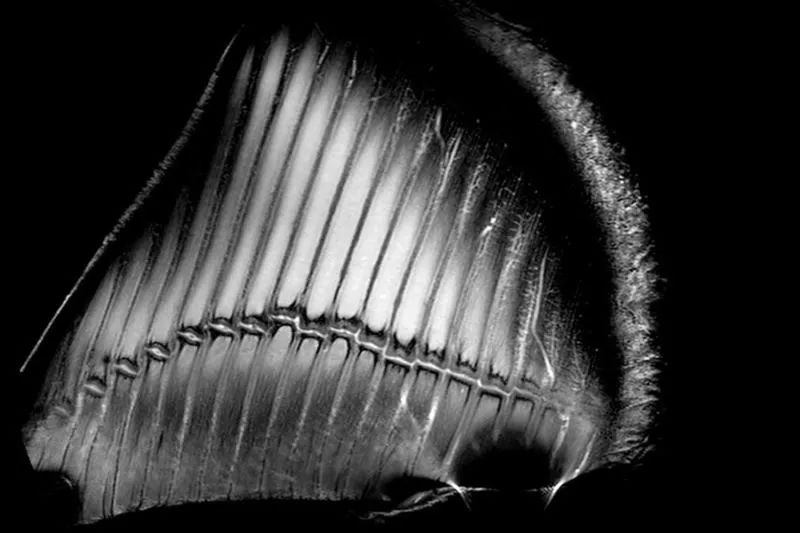

△ 根据BBC的报道,这是世界上关于大脑连接的最精细的图像。在这张图里你看到的是白质(连接脑区的神经纤维束)的形态。在这些通道里传导的是神经信号,也就是你的思想。这张图的制作者是英国卡迪夫大学脑成像研究的研究人员。